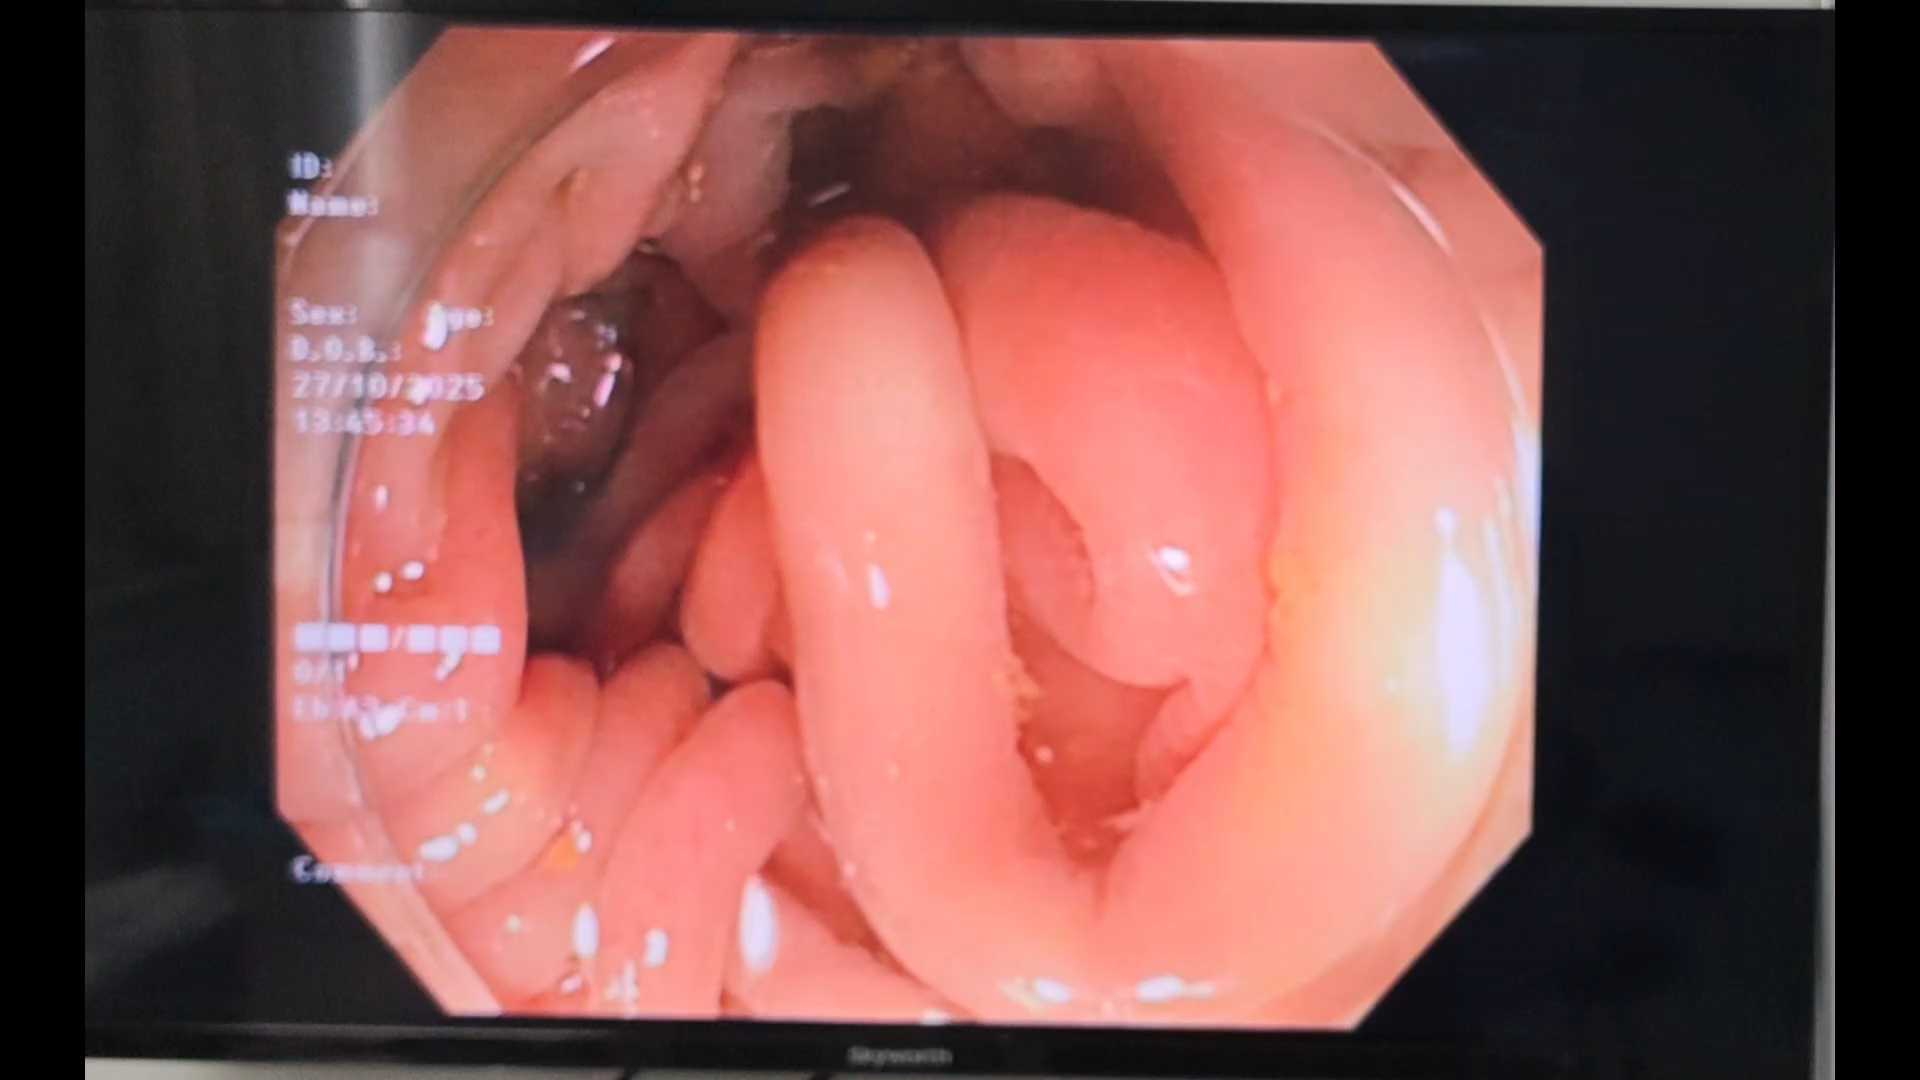

患者66岁,便秘伴腹胀5年余之主诉入院,行胃肠镜检查。肠镜退镜至降结肠处所见如视频:

内镜检查的形态学特征如下:表面由正常黏膜覆盖,是细长的有蒂型病变,表现为“蠕虫状”外观或呈“蚯蚓状”或细绳状或棍棒状的形态,表面发红,伴有糜烂,呈现脑回状或小结节状。